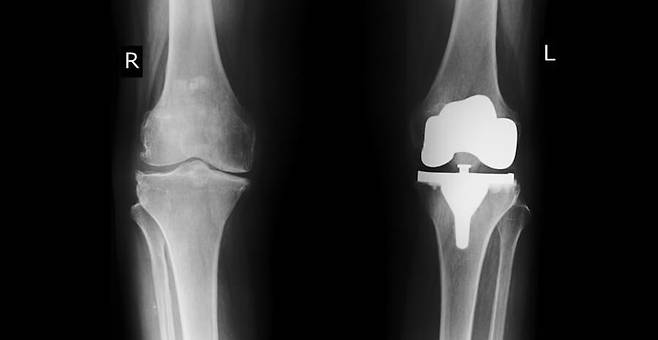

무릎에 불편함이 생기면 일상 전체가 달라지죠. 계단을 오를 때마다 찌릿한 통증이 오고, 걷는 것도 점점 힘들어진다면 결국 수술까지 고민하게 되는데요. 인공관절 수술은 비용이 적지 않아 망설여지는 것도 사실이에요. 오늘은 무릎인공관절수술비용부터 회복까지, 궁금한 부분들을 하나하나 정리해봤어요.

수술비는 병원과 수술 방식, 사용하는 인공관절의 종류에 따라 크게 달라져요. 일반적으로 한쪽 무릎 기준 250만 원에서 400만 원 사이가 평균적이고, 양쪽을 동시에 수술하게 되면 600만 원을 넘는 경우도 많답니다. 서울의 대형 병원에서는 1,000만 원 이상 청구되는 사례도 있어서, 사전에 견적을 꼭 확인해보는 게 좋아요. 반면 지방의 중소병원은 평균 400만 원 내외로 조금 더 저렴한 편이에요.

최근에는 일반 수술보다 정밀도가 높은 로봇 수술을 도입한 병원도 많아지고 있어요. 로봇이 의사의 손을 도와 더 정확하게 절개하고 맞춤형 삽입이 가능하다는 장점이 있지만, 그만큼 비용은 상승해요. 로봇 수술은 평균 600만 원 이상, 경우에 따라 900만 원에 달하기도 하죠. 따라서 본인의 무릎 상태와 예산을 잘 고려해서 결정하는 게 필요해요.